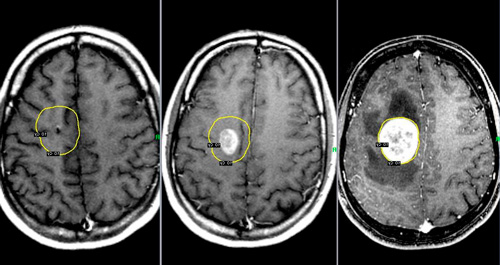

Злоякісні новоутворення в головному мозку

Причиною поганого самопочуття, закладеності вуха і запаморочення можуть виявитися пухлини мозку. Небезпека такого стану в тому, що пацієнти звертаються за лікарською допомогою при явних ознаках хвороби, а це вже не перша стадія захворювання, що ускладнює лікування.

Під час першого нападу закладеності у вухах і запаморочення складно зрозуміти, чим це викликано. Щоб визначити можливі причини, слід звернутися до лікаря. Він перевірить стан судин, призначивши томографію, УЗД і рентгенологічне дослідження.

- хірургічне втручання рекомендують при пухлинах мозку, стенозі судин.